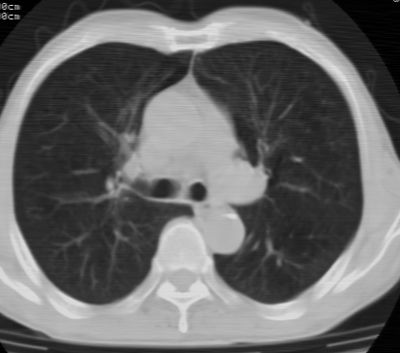

1、左肺上叶spn,毛刺+分叶+血管集束征,考虑周围型肺癌可能性大

2、全小叶性肺气肿。

1)左肺上叶周围型肺癌可能。2)两肺全小叶型肺气肿。

左上周围型肺癌,全小叶型肺气肿。